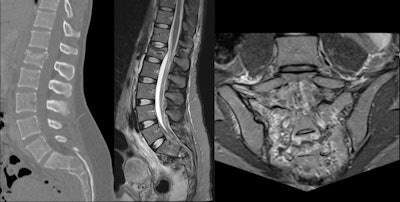

A 28-year-old woman suffered trauma during sledging. Acute fracture of L1 vertebral body with height loss and small backward retreat of posterior wall, as well as multifragmentary sacral fracture, prevertebral, and presacral hematomas. Residual right L5 radiculopathy after surgical fixation."Spinal injuries are a major cause of permanent disability and appear to be increasing among skiers and snowboarders," the researchers said. "Spinal injuries in skiers have been traditionally much less common than in snowboarders, but this disparity is likely to diminish with the recent trend of incorporating snowboarding moves into skiing."

Thoracolumbar spine injuries are more common than cervical spine or sacral lesions. Anterior thoracolumbar abnormalities are a result of excessive loading of the spine, which increases when the athlete is flexed forward. Because elite skiers begin training at an early age, it is likely that the anterior endplate lesions are a result of an imbalance between the applied load and the loading capacity of the immature spine.